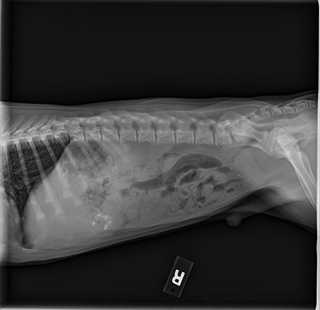

Fortunately, the 2V abdominal series (twice) only demonstrated gastric and colon gravel and treatment was basically time and probiotics.